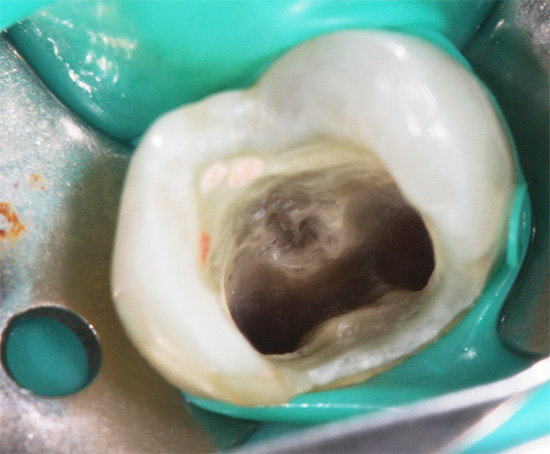

Foto de polpa removida de um dente:

Os dentistas modernos para o tratamento da pulpite fibrosa crônica de qualquer dente escolhem o método de extração completa da polpa dos canais sob anestesia eficaz. Após um bom "congelamento", a parte coronal do "nervo" é removida primeiro e, em seguida, a raiz é removida com a ajuda de extratores de polpa (agulhas finas que permitem a remoção da polpa devido a ganchos especiais). Depois disso, o dentista realiza a passagem e expansão dos canais com limas (ferramentas com arestas de corte e alça para segurar), juntamente com o tratamento medicamentoso de todos os ramos do canal com soluções anti-sépticas.